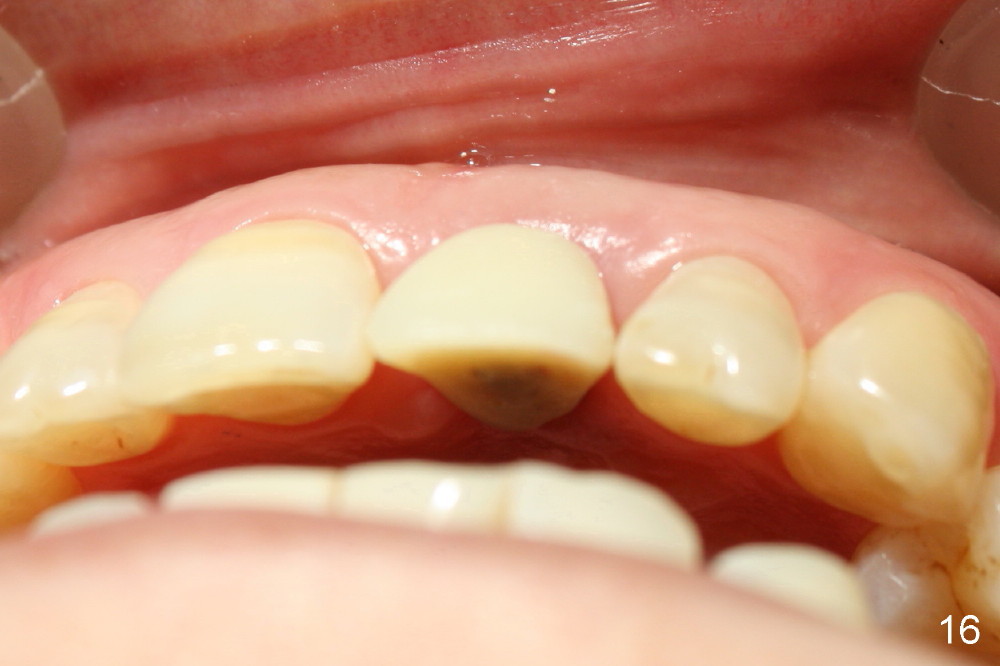

A 60-year-old lady had an abscess mesial to #9 six years ago (Fig.1,2 <), treated as a perio lesion by laser (Fig.3) and osseous surgery without bone graft (Fig.6, followed by CT exam revealing semi-circumferential bone loss (Fig.4,5). When the perio treatment failed, attention was paid to endo aspect (Fig.7-9). In fact the pulp was found to be vital when access to root canal therapy was made. As expected, the treatment failed again. The palatal fistula persisted. The infection was suspected to be a source of remote immediate implant site (#30). The tooth #9 was extracted. It appears that there is a semilunar crack line in the linguomesial root (Fig.12). When the socket healed 2 weeks post extraction (Fig.10), the #30 buccal defect was debrided with bone graft. There was no bone resorption 4 weeks post extraction (Fig.11); a 4.5x17 mm implant was placed (Fig.13-15). An immediate provisional was fabricated (Fig.16-18). Fig.19,20 were taken 3 months post implantation and 7 months post cementation, respectively. Dense bone forms around the implant coronally 4 years 5 months post cementation (Fig.21), while the gingiva is healthy palatally (Fig.22) and buccally (Fig.23).